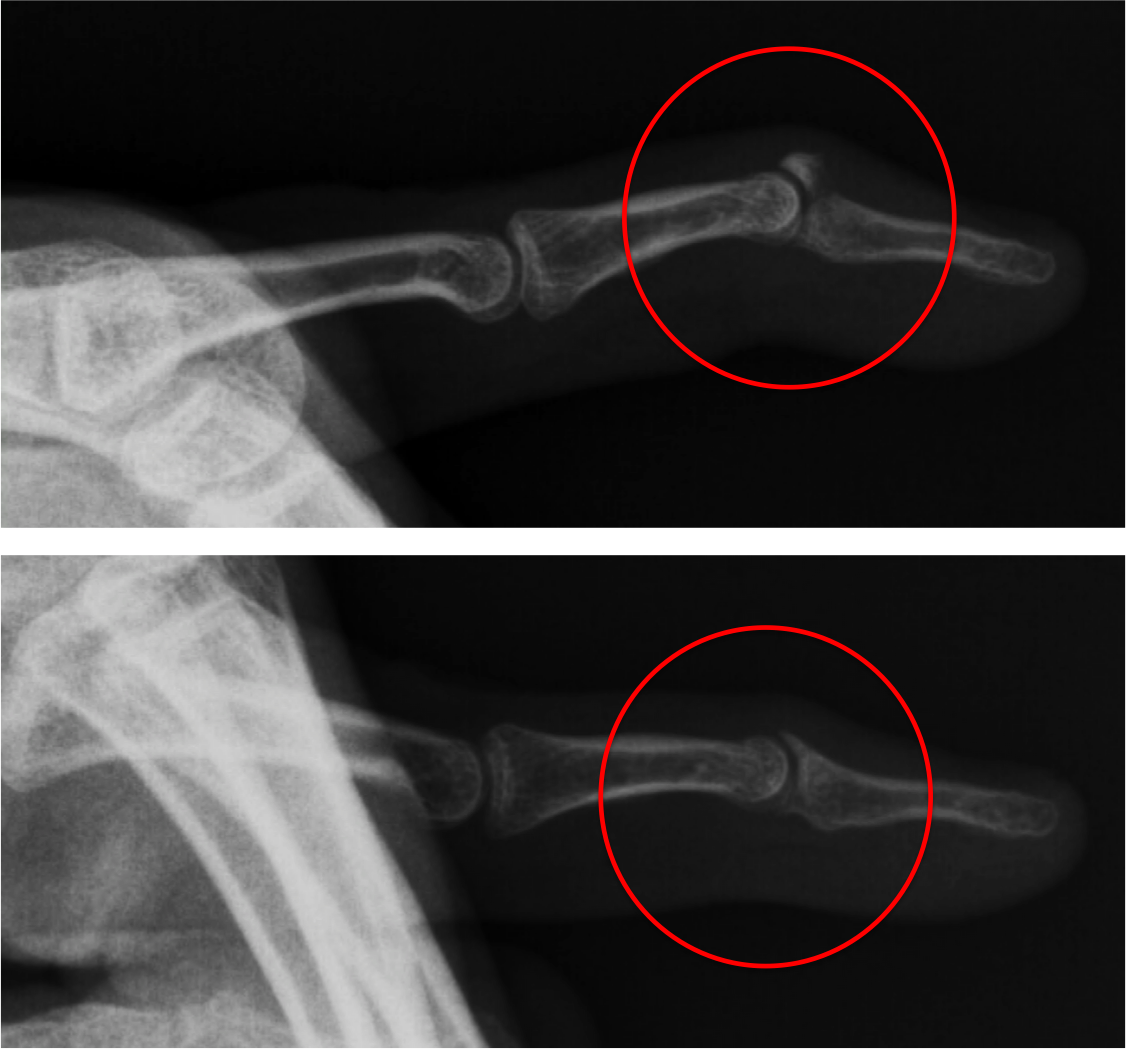

Mallet Finger Deformity Xray . Mallet finger is a flexion deformity of the finger that results from injury to the extensor mechanism of the distal phalanx. Avulsed fracture at the base of the distal phalanx of the right middle finger with mallet finger deformity. A mallet finger is a deformity of the finger typically caused by injury. The diagnosis of a mallet finger is usually a clinical diagnosis. Look for evidence of an avulsion fracture on the dorsal aspect of the base of the distal phalanx (=bony mallet). However, to distinguish between mallet finger injuries and. After the fingertip gets jammed, the end (smallest) joint of the finger just before the fingernail droops and looks. Mallet finger is a finger deformity caused by disruption of the terminal extensor tendon distal to dip joint. Soft tissue swelling is noted.

Mallet Finger Deformity Xray Avulsed fracture at the base of the distal phalanx of the right middle finger with mallet finger deformity. After the fingertip gets jammed, the end (smallest) joint of the finger just before the fingernail droops and looks. Soft tissue swelling is noted. Look for evidence of an avulsion fracture on the dorsal aspect of the base of the distal phalanx (=bony mallet). The diagnosis of a mallet finger is usually a clinical diagnosis. Avulsed fracture at the base of the distal phalanx of the right middle finger with mallet finger deformity. Mallet finger is a flexion deformity of the finger that results from injury to the extensor mechanism of the distal phalanx. A mallet finger is a deformity of the finger typically caused by injury. However, to distinguish between mallet finger injuries and. Mallet finger is a finger deformity caused by disruption of the terminal extensor tendon distal to dip joint.